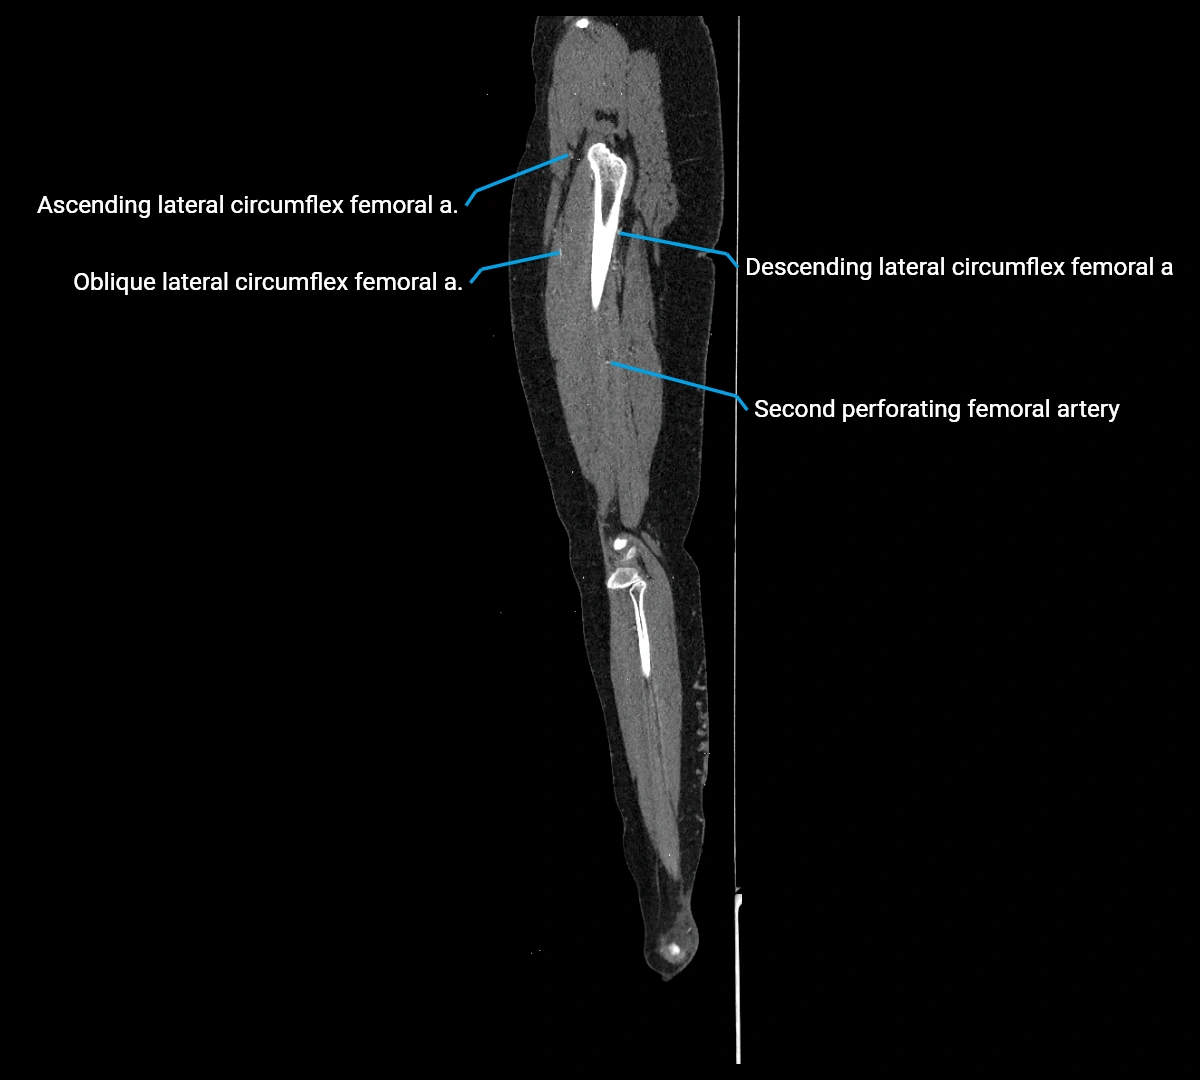

CT images

image

Contrast-enhanced CT (CTA):

• Gold standard for abdominal aortic imaging

• Provides excellent detail of lumen, wall, aneurysm, thrombus, and branch vessels

• Multiplanar and 3D reconstructions help in aneurysm measurement, stent graft planning, and dissection evaluation

• Detects acute rupture, traumatic injury, or occlusion with high sensitivity